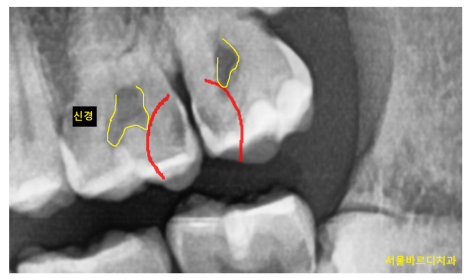

일반적으로는 충치 부위가 클 수록

파내는 범위 역시 넓고 깊기 때문에 시림이 발생할 확률이 높습니다.

특히나 치아 신경과 가까운 충치일수록 말이죠

250429 치아의 2/3 이상 충치가 침범하였을 때 통증을 느끼는 경우가 많습니다 .